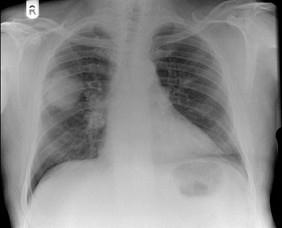

58岁,男,咳嗽、气促3个月,抽烟20余年,请结合胸片图,选择最可能的诊断 ( )A.肺癌B.胸膜间皮瘤C.肺结核D.错构瘤E.结节病

问题 58岁,男,咳嗽、气促3个月,抽烟20余年,请结合胸片图,选择最可能的诊断 ( )

选项 A.肺癌 B.胸膜间皮瘤 C.肺结核 D.错构瘤 E.结节病

答案 A